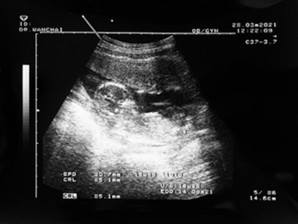

ทางนี้ 14w5d ค่ะ กำหนดคลอด 24 กันยา ออกแนวกังวลมากกว่า กลัวลูกไม่แข็งแรง กลัวกินนั่นกินนี่แล้วจะไม่ดีกับลูก กลัวลูกน้ำหนักตัวน้อย กลัวไปหมด ขนาดตอนไปตรวจคัดกรองดาวน์ซินโดรมรอผล 10 วันแม่ไมเกรนขึ้นเลยค่ะ พะวงไปหมด พอผลออกมาโล่งมากได้ลูกสาวสมใจคุณพ่อด้วยค่ะ 😊